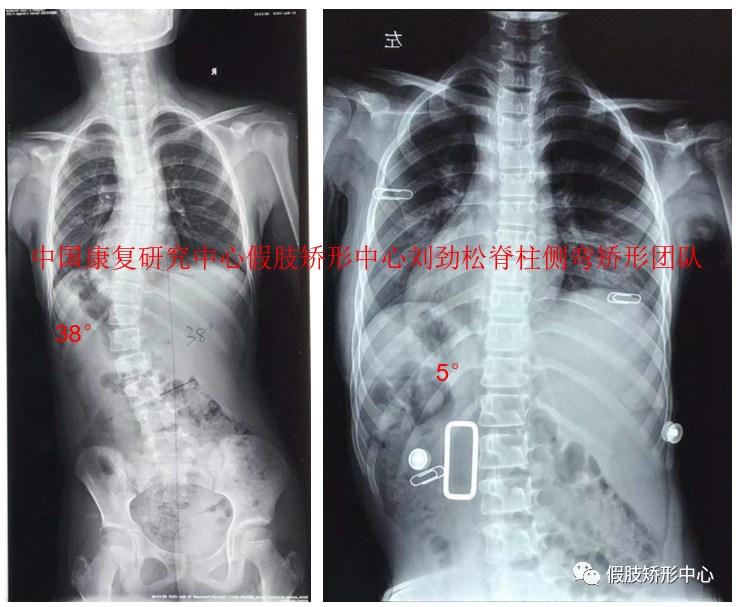

SCS脊柱側(cè)彎矯形器個(gè)案